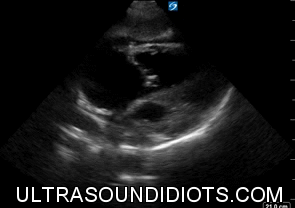

Echo Subcostal Exams